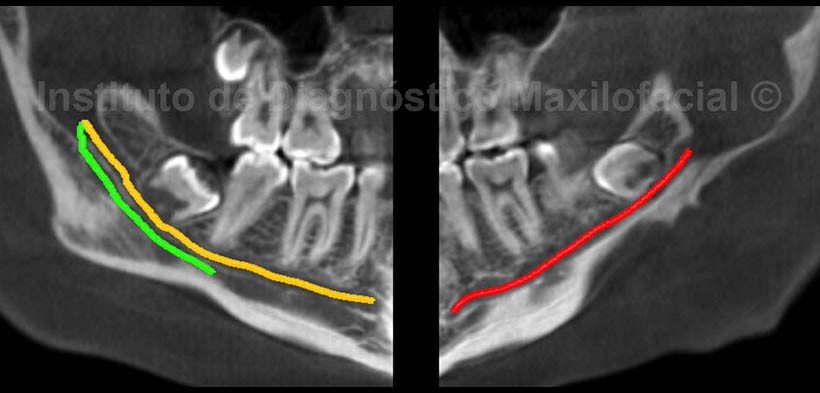

En los cortes tangenciales (Fig.4) y transaxiales (Fig.5), se han delimitado los conductos dentarios inferiores de ambos lados, ilustrando de color amarillo el conducto del lado derecho; por otro lado, se aprecia un conducto dentario accesorio que se extiende desde el agujero mandibular hasta el nivel de la pieza 4.7, el cual hemos ilustrado de color verde. Así mismo, en el lado izquierdo se observa la delimitación del conducto dentario inferior de color rojo, evidenciándose una considerable ampliación a nivel de la entrada del paquete vasculonervioso, el cual esta en relación con una imagen hipodensa de limites definidos.